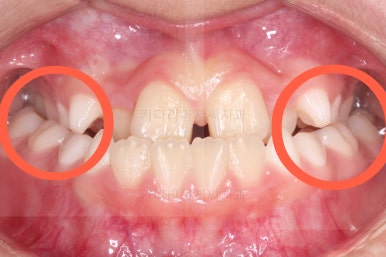

마찬가지로 초진 시 입안의 모습이에요.

아래 앞니가 윗니보다 앞에 있는 "반대교합" 즉, 거꾸로 물려있는 상황이었고요.

어금니 쪽을 보시면(왼쪽 위 사진) 윗니 어금니도 아래 어금니보다 안쪽으로 들어와 있는 "어금니 반대교합"도 있는 상황이었어요.

즉, 윗니가 있는 위턱뼈가 3차원적으로 작은 상황이었던거죠.

이렇게 아랫니들이 윗니보다 앞으로 나와있는 형태의 부정교합을 "앵글씨 3급" 부정교합이라고 합니다.